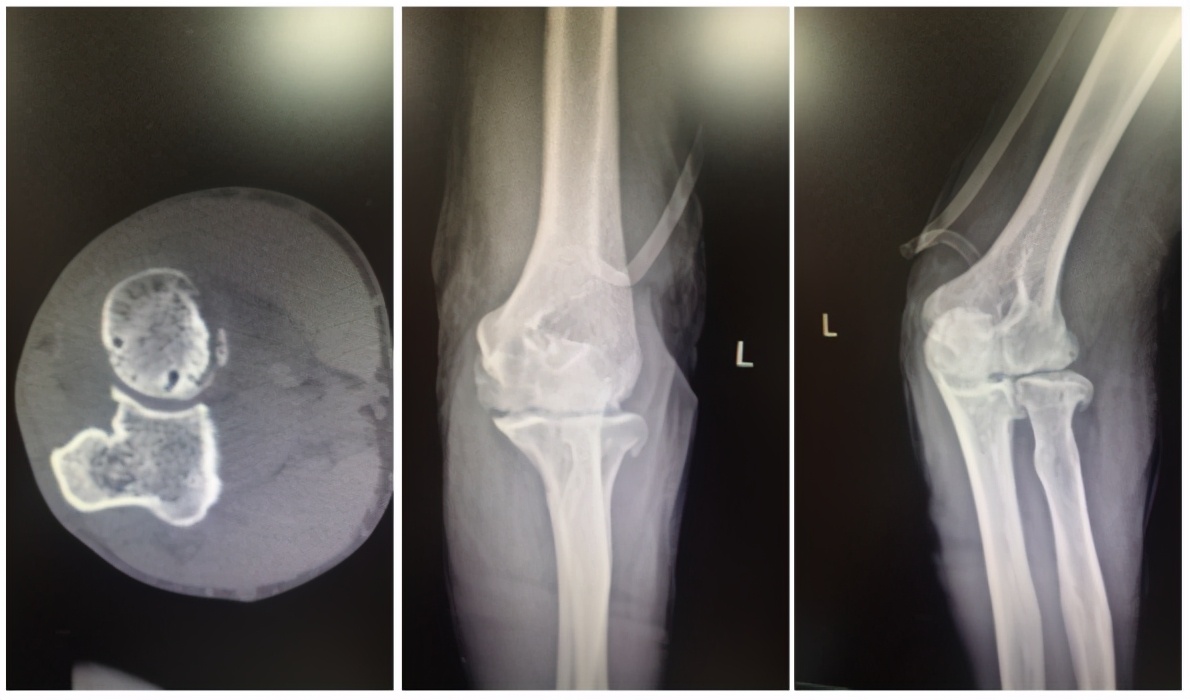

郭阿伯关节影像图

长期受痛风折磨,郭阿伯的关节早已“千疮百孔”,通过影像学可见到关节间隙变窄,游离体形成,关节表面软骨破坏,骨质增生明显,骨性关节面不光整,关节面下可见囊状骨质破坏,手术治疗已经迫在眉睫。